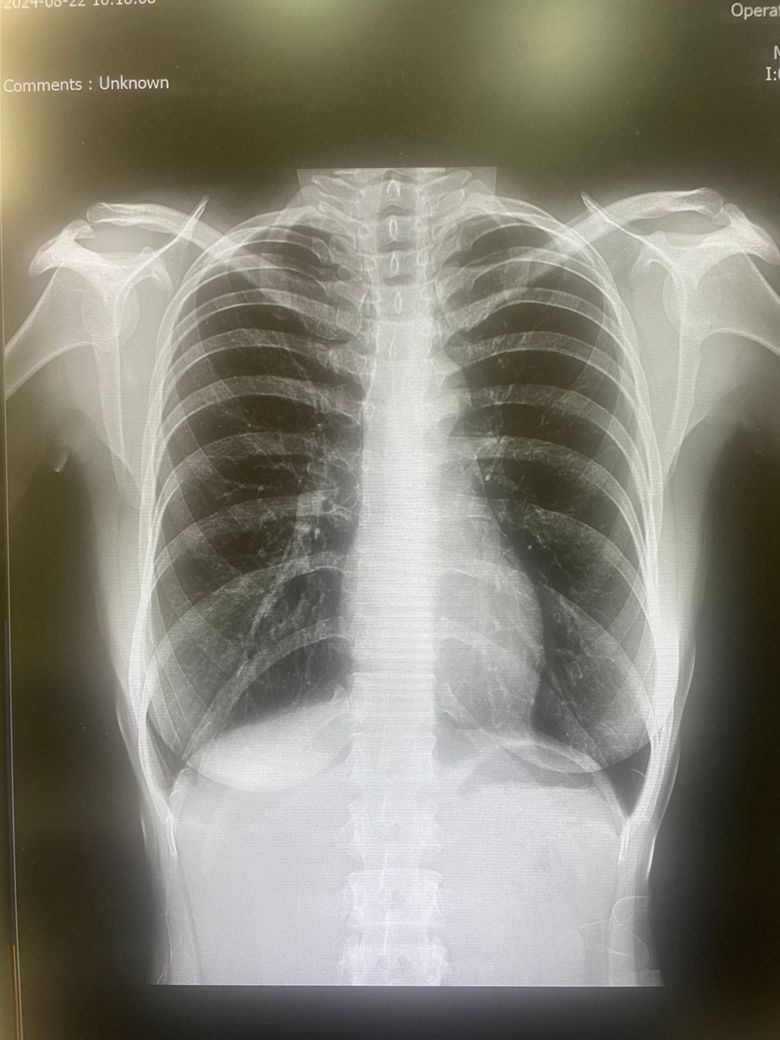

아침에 일어나서 침뱉을때 피가 나서 폐엑스레이를 찍어봤는데 괜찮은가요?

저번달부터 침뱉을때 노란침과 아주 소량의 실핏줄같은 피가 섞여서 나와서 폐 엑스레이를 찍어봤는데 괜찮아보이나요? 숨차거나 기침을하거나 그런건 없고 나이가 젊지만 흡연을 좀 오래해서 걱정이 되네요 (13년정도)

• 1번 째 사진

침을 밷을 때 피가 섞여 나왔다면 먼저 치과 검진을 받아보시고 치주 질환 등 이상이 없는데도 증상이 반복 시 정밀 검사를 위해 흉부 CT 검사를 권합니다.